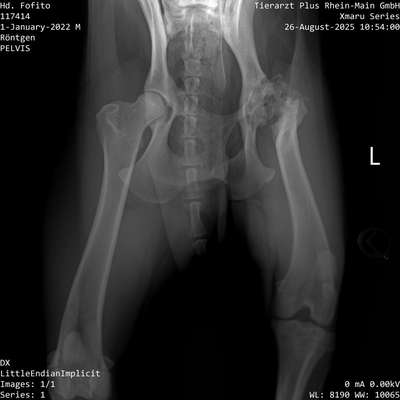

Hallo miteinander 🙂 habt ihr schon mal so eine schlechte Hüfte gesehen? Ich sage immer, mein Hund mit ohne Hüfte. Das betroffene Bein nutzt er quasi nur als Stütze, es ist deutlich weniger bemuskelt als die andere Seite. Er kann sich auch nicht auf die betroffene Seite legen,. Aber kann rennen und toben wie jeder andere Hund. Eine OP ist nicht möglich, da der Knochen so dünn ist, dass kein neues Gelenk halten würde. Bei kleineren/ leichteren Rassen gibt es noch die Möglichkeit den Femurkopf zu entfernen. Aber davon haben uns 3 Tierärzte abgeraten, da Fito mit seinen 43 kg zu schwer wäre. Hat jemand damit Erfahrung?